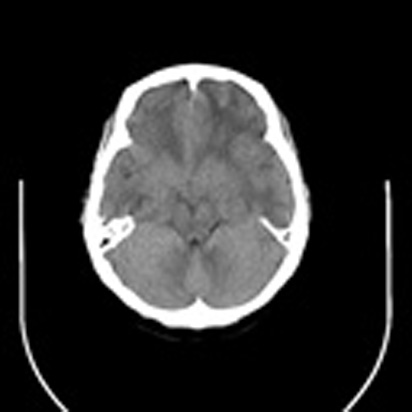

标题: CT16829:女,36,近20天偶有口眼歪斜短暂发作史,近日头痛。 [打印本页]

标题: CT16829:女,36,近20天偶有口眼歪斜短暂发作史,近日头痛。

近20天偶有口眼歪斜短暂发作史,近日头痛。患者先做ct发现病变后又做了mri检查,前日上传2次ct图像均未成功,今日补上。

左额混杂密度肿块,经胼胝体跨越中线向右额叶生长,多考虑少支胶质细胞瘤,建议mr增强扫描,待排除血管畸形。